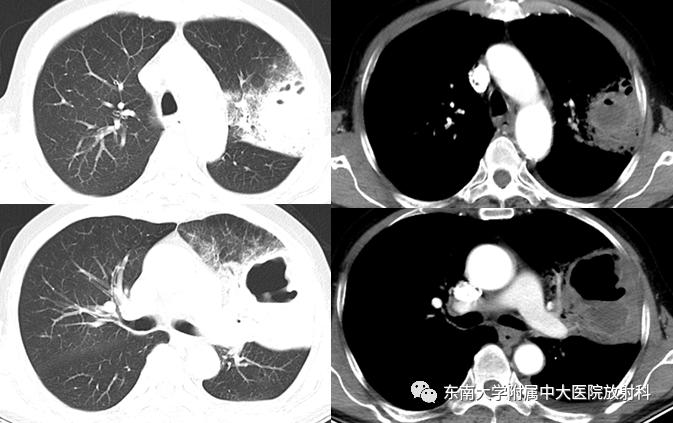

【病例】肺脓肿1例ct影像